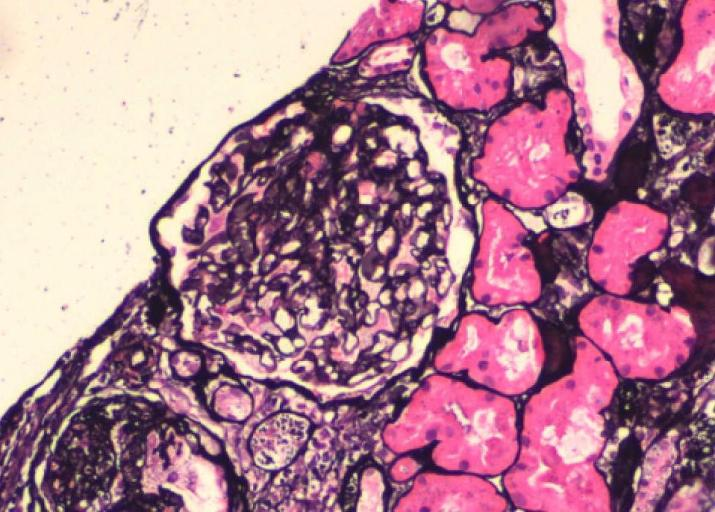

PASM×200

Masson×200 肾小球上皮细胞肿胀伴空泡变性、泡沫细胞形成

光镜:肾小球上皮细胞肿胀伴空泡变性、泡沫细胞形成(神经鞘脂沉积);甲苯胺蓝染色可见嗜甲苯胺蓝颗粒在足细胞、小管上皮细胞以及壁层上皮细胞多部位沉积。